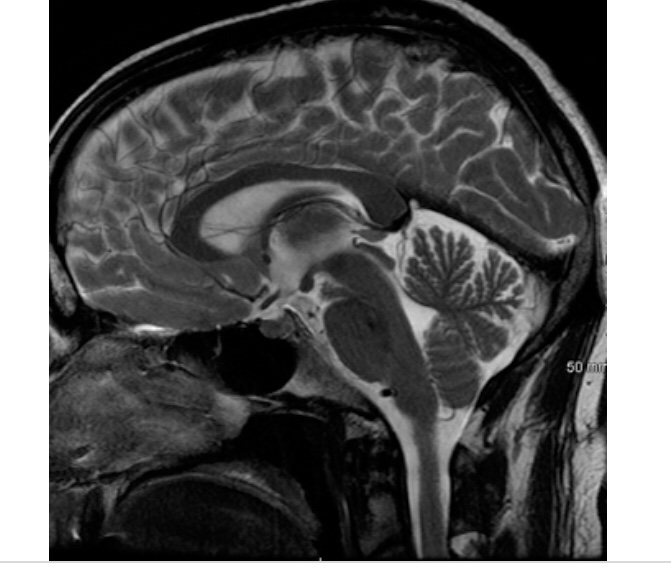

My doctor walked in and I rambled about my plethora of symptoms and my suspicions about MS. She has only been my doctor for a year so I had no idea how she would respond. She thoroughly read my three page description of symptoms and was supportive of my decision to investigate. She ordered a long list of blood work, an ecg and a brain MRI. As well, she referred me to a Neurologist in the city. It’s hard to believe that I could be excited about searching for a diagnosis, but I am. There is something incredibly freeing about choosing to no longer live in denial.Â